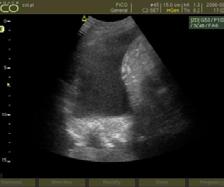

Metastaze pulmonare. Examen CT multislice, fereastră pulmonară, plan axial.

Din colecția Centrului de Imagistică, UMFCV

Tumoră rectală. Examen IRM, secvența T2 ponderată, plan sagital.